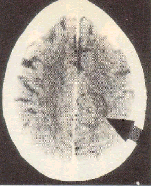

CT mit einem Hamerschen Herd in beginnender Lösungsphase.

In der konflikt-aktiven Phase stets mit scharf markierten Kreisen, als sog. Schießscheiben-konfiguration, und in der konflikt-gelösten Phase ist der Hamersche Herd aufgequollen, oedematisiert.

In der konflikt-aktiven Phase stets mit scharf markierten Kreisen, sog. Schießscheiben-konfiguration, und in der konflikt-gelösten Phase ist der Hamersche Herd aufgequollen, oedematisiert.